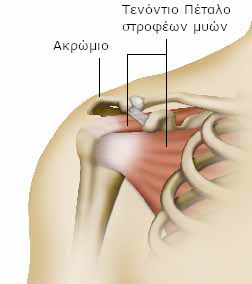

Ένα άλλο μέρος της ωμοπλάτης, το ακρώμιο σχηματίζει ένα θόλο πάνω από την άρθρωση. (Είναι το μικρό εξόγκωμα που μπορούμε να αισθανθούμε βάζοντας το χέρι πάνω από τον ώμο μας).

Πολλοί μύες, οι οποίοι συνδέονται με τα οστά μέσω των τενόντων, περιβάλλουν την άρθρωση και επιτρέπουν τις κινήσεις.

Ανάμεσα σε αυτούς τους μυς, αυτοί που σχηματίζουν το ονομαζόμενο τενόντιο πέταλο των στροφέων μυών, περνούν ανάμεσα από το ανώτερο μέρος του βραχιονίου και κάτω από το ακρώμιο.

Αυτοί οι μύες πρέπει να λειτουργούν αρμονικά, ώστε ο ώμος να περιστρέφεται προς οποιαδήποτε κατεύθυνση, διατηρώντας το κέντρο του.